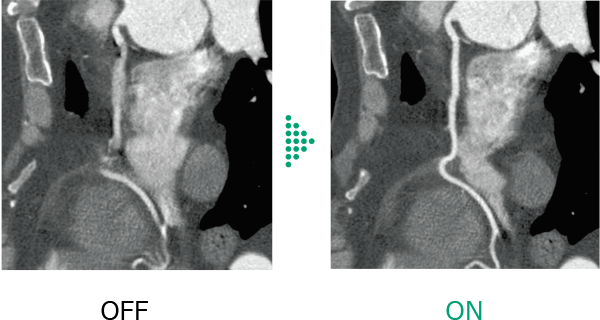

Conventional cardiac CT scans*1 were affected by changes in heart rate during scanning, such as high heart rates and arrhythmias, which affected the image quality of the entire heart and make diagnosis difficult in some cases.

Cardio StillShot*4 calculates the direction and amount of patient motion in four dimensions from the collected raw data and provides images with minimal motion blur due to motion . By applying corrections during image reconstruction, it achieves an effective temporal resolution of up to 28 milliseconds*5.